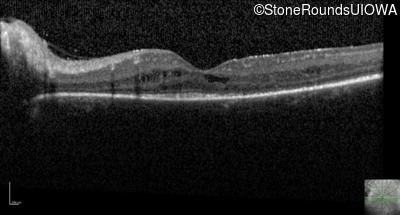

Optical Coherence Tomography - Right - 20/30 -1

Exemplar / OCT Stack